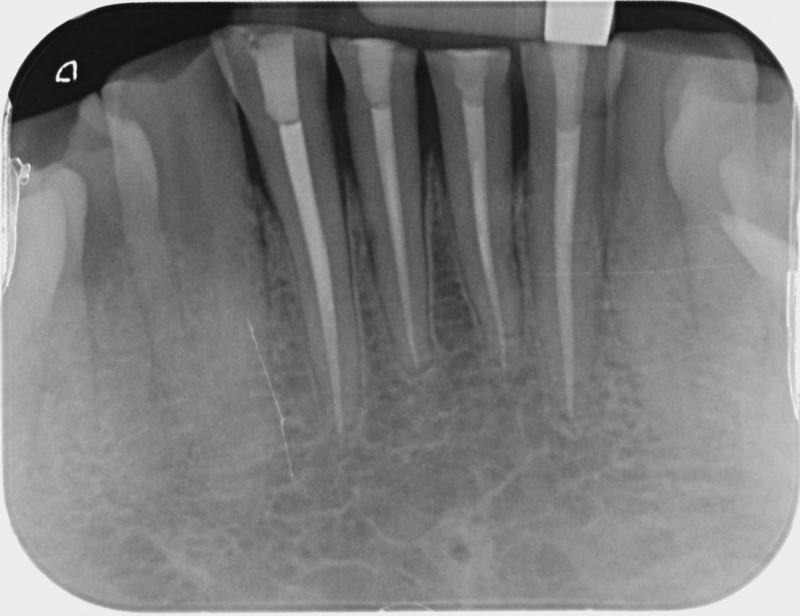

• Traitement endodontique : Sous anesthésie locale et à travers la protection d’un champ opératoire nous accédons à la pulpe de la dent à soigner, puis aux canaux de ses racines que nous devons désinfecter. Ce soin nécessite l’élimination complète de la source de contamination (souvent la carie) parfois sous une ancienne reconstitution ou une couronne qu’il faut alors retirer. Une fois le nettoyage et la mise en forme des canaux réalisés, nous les obturons de façon hermétique avec un ciment et un matériau thermoplastique appelé Gutta Percha. Ceci afin d’empêcher une nouvelle prolifération bactérienne et d’assurer le maintien de la dent dans ses structures de soutien (ligament parodontal et os alvéolaire). L’ouverture effectuée au centre de la dent sera d’abord refermée avec un pansement provisoire avant d’envisager ensemble la reconstitution d’usage : un composite, un inlay-onlay ou une couronne.

Avant